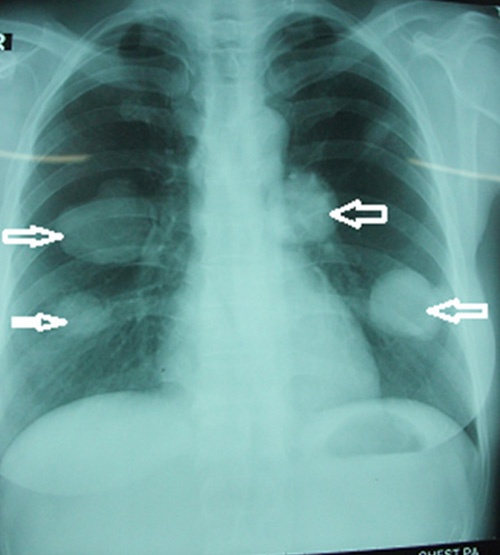

| Chụp hình ảnh bệnh nhân ở Thanh Hóa bị sán chó làm tổ tạo u trong phổi. |

Bệnh nhân nhập viện Lao phổi Trung ương để điều trị, kết quả chụp X-quang cho thấy bệnh nhân có 4 khối u khổng lồ trên phổi.

Đây là trường hợp rất nguy hiểm, bởi mỗi bên phổi bệnh nhân có 2 khối u và không thể phẫu thuật. Nếu cắt sẽ phải cắt toàn bộ phổi và bệnh nhân sẽ tử vong ngay. Các bác sĩ đã chọc dò hút dịch để kiểm tra thì thấy hàng nghìn đầu sán ở mỗi ổ.